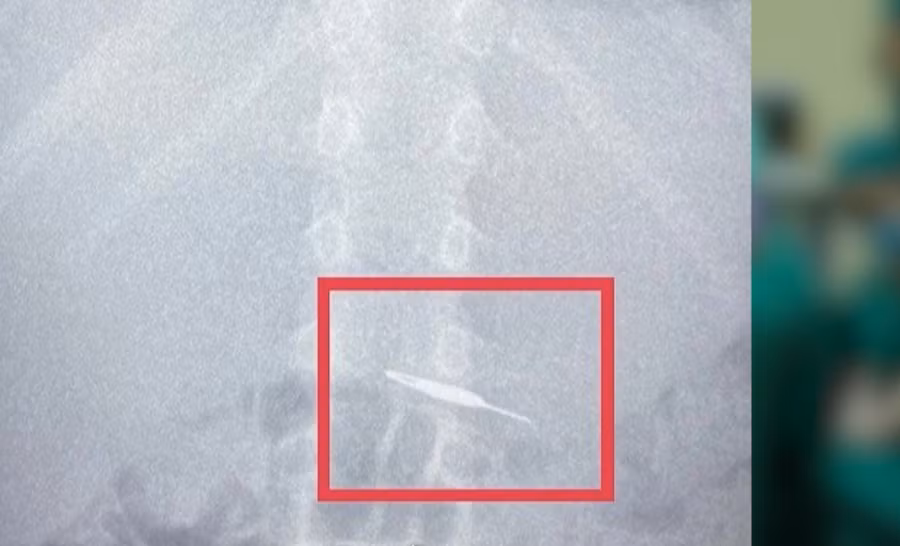

Hình ảnh que chọc sim trong bụng bé trai 7 tuổi.

Trên phim chụp X-quang, các bác sĩ phát hiện trong ổ bụng có dị vật sắc nhọn và nhận định nếu không lấy ra kịp thời có thể gây nguy hiểm cho bé. Ê kíp cấp cứu nhanh chóng đưa ra chỉ định cần nội soi gắp dị vật ra ngoài ngay lập tức.

Trong quá trình nội soi, các bác sĩ phát hiện dị vật kim loại (que chọc sim) có kích thước 5cm. Để gắp que chọc sim có 1 đầu sắc nhọn, các bác sĩ khoa Nội soi phải dùng dụng cụ chuyên dụng.

Quá trình nội soi gắp dị vật diễn ra an toàn, kiểm tra không ghi nhận chảy máu. Cháu bé đã an toàn sau khi được can thiệp lấy dị vật.